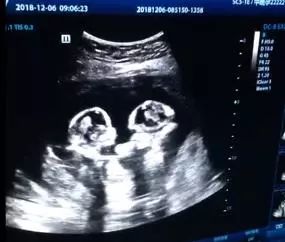

您的位置:長(zhǎng)沙社區(qū)通 > 新聞 > 國(guó)內(nèi) > 視頻 > 銀川一對(duì)雙胞胎在媽媽肚子里打架!視頻太有趣了

銀川一對(duì)雙胞胎在媽媽肚子里打架!視頻太有趣了

4月8日,一對(duì)單絨單羊雙胎寶寶在媽媽肚子里“打架”的視頻,經(jīng)抖音傳播迅速吸引來(lái)245.6萬(wàn)的點(diǎn)贊量和6000多萬(wàn)的觀(guān)看數(shù)量,一時(shí)成為焦點(diǎn)。懂醫(yī)學(xué)知識(shí)的人都知道,這種單絨單羊雙胎非常罕見(jiàn),胎兒發(fā)生危險(xiǎn)的幾率也很高,大家都為這對(duì)雙胞胎順利降生捏了一把汗。4月11日,記者從這對(duì)雙胞胎的父親陶先生口中得知,女兒們?cè)?月8日下午順利出生,目前情況良好。這也成為寧夏醫(yī)科大學(xué)總醫(yī)院第一例順利出生且存活下來(lái)的單絨單羊雙胎寶寶。

4月11日下午,記者在寧醫(yī)大總院見(jiàn)到陶先生,他每天除了照顧媳婦,還要去新生兒科給孩子們送母乳,詢(xún)問(wèn)孩子的健康狀況。坐在產(chǎn)科候診區(qū)的凳子上,陶先生向記者展示了這段視頻,視頻是去年年底妻子產(chǎn)檢時(shí)的B超影像,只見(jiàn)左邊的寶寶先動(dòng)手,右邊的立馬還擊,兩人幾個(gè)回合互不相讓?zhuān)倥湟月蓜?dòng)的音樂(lè),有種看拳擊賽的感覺(jué),既搞笑又可愛(ài)。視頻下方的留言里“心疼”“好可愛(ài)”“好神奇”“好萌”等都是高頻詞,還有人留言也想生雙胞胎寶寶。陶先生笑著說(shuō),他當(dāng)時(shí)發(fā)到抖音里就是覺(jué)得好玩,沒(méi)想到關(guān)注度會(huì)這么高,“孩子還沒(méi)出生就成網(wǎng)紅了”。

陶先生介紹,雖然小的體重輕,但不影響小家伙在媽媽肚子里“耍寶”,大的明顯更安靜,只是偶爾翻一下身。兩人除了在媽媽肚子里打架淘氣外,也有相親相愛(ài)溫馨的一面。“今年1月22日,妻子做羊水穿刺的時(shí)候,小的靠著大的,大的摟著小的,把我們感動(dòng)得稀里嘩啦,這么一點(diǎn)點(diǎn)的孩子就知道相互關(guān)心,相信孩子們長(zhǎng)大了一定相處得很和睦。”陶先生微笑著說(shuō)。